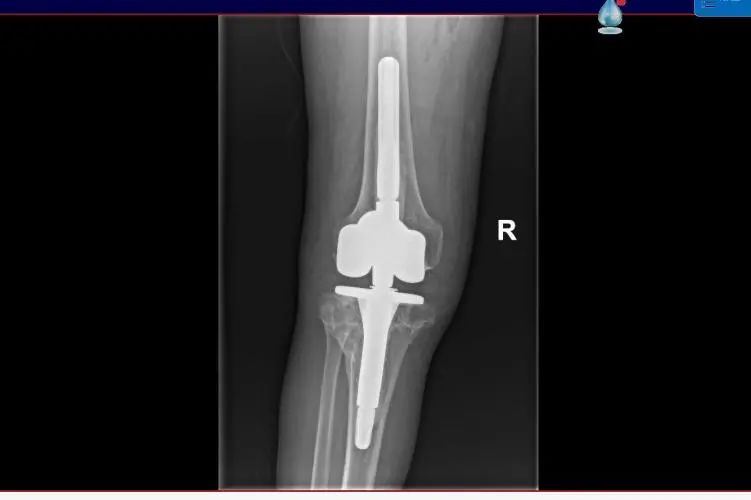

12日,手术顺利完成,尤大叔患者膝关节的运动功能恢复良好,手术后第一天就开始进行床上屈伸活动,第二天开始逐渐下地站立、行走。据了解,尤大叔将于11月16日出院。

▲术后影像

“太感谢专家了,没想到困扰我九年多的问题,入院一个礼拜就解决了?!庇却笫寮ざ乇硎?,原先的状态连最简单的站立都无法做到,术后仅三天就已经能够下地行走了。